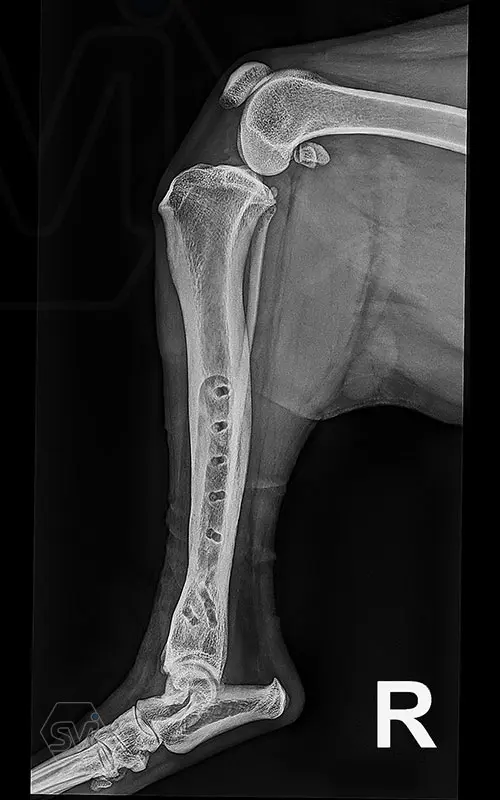

Multifunctional symmetrical long polyaxial locking plate - designed for the treatment of fractures close to joints

A special member of the polyaxial locking plate family is the multifunctional long plate, which is an extended version of the well-known symmetrical TPLO plate, with a 5-3 hole distribution. The plate also received a DCP hole to be able to create compression, and there is a mini-hole on the head end to facilitate the placement of the temporarily used K-nail. The burrs on the side facing the bone surface are intended to reduce the contact surface between the plate and the bone (limited contact).

The plate is a member of the large polyaxial locking family, suitable for 2.7-3.5-4.0 mm screws. We recommend it for fixaton of fractures close to joints, wedge osteotomies with axis correction (closing and opening), or for CWTO operations.